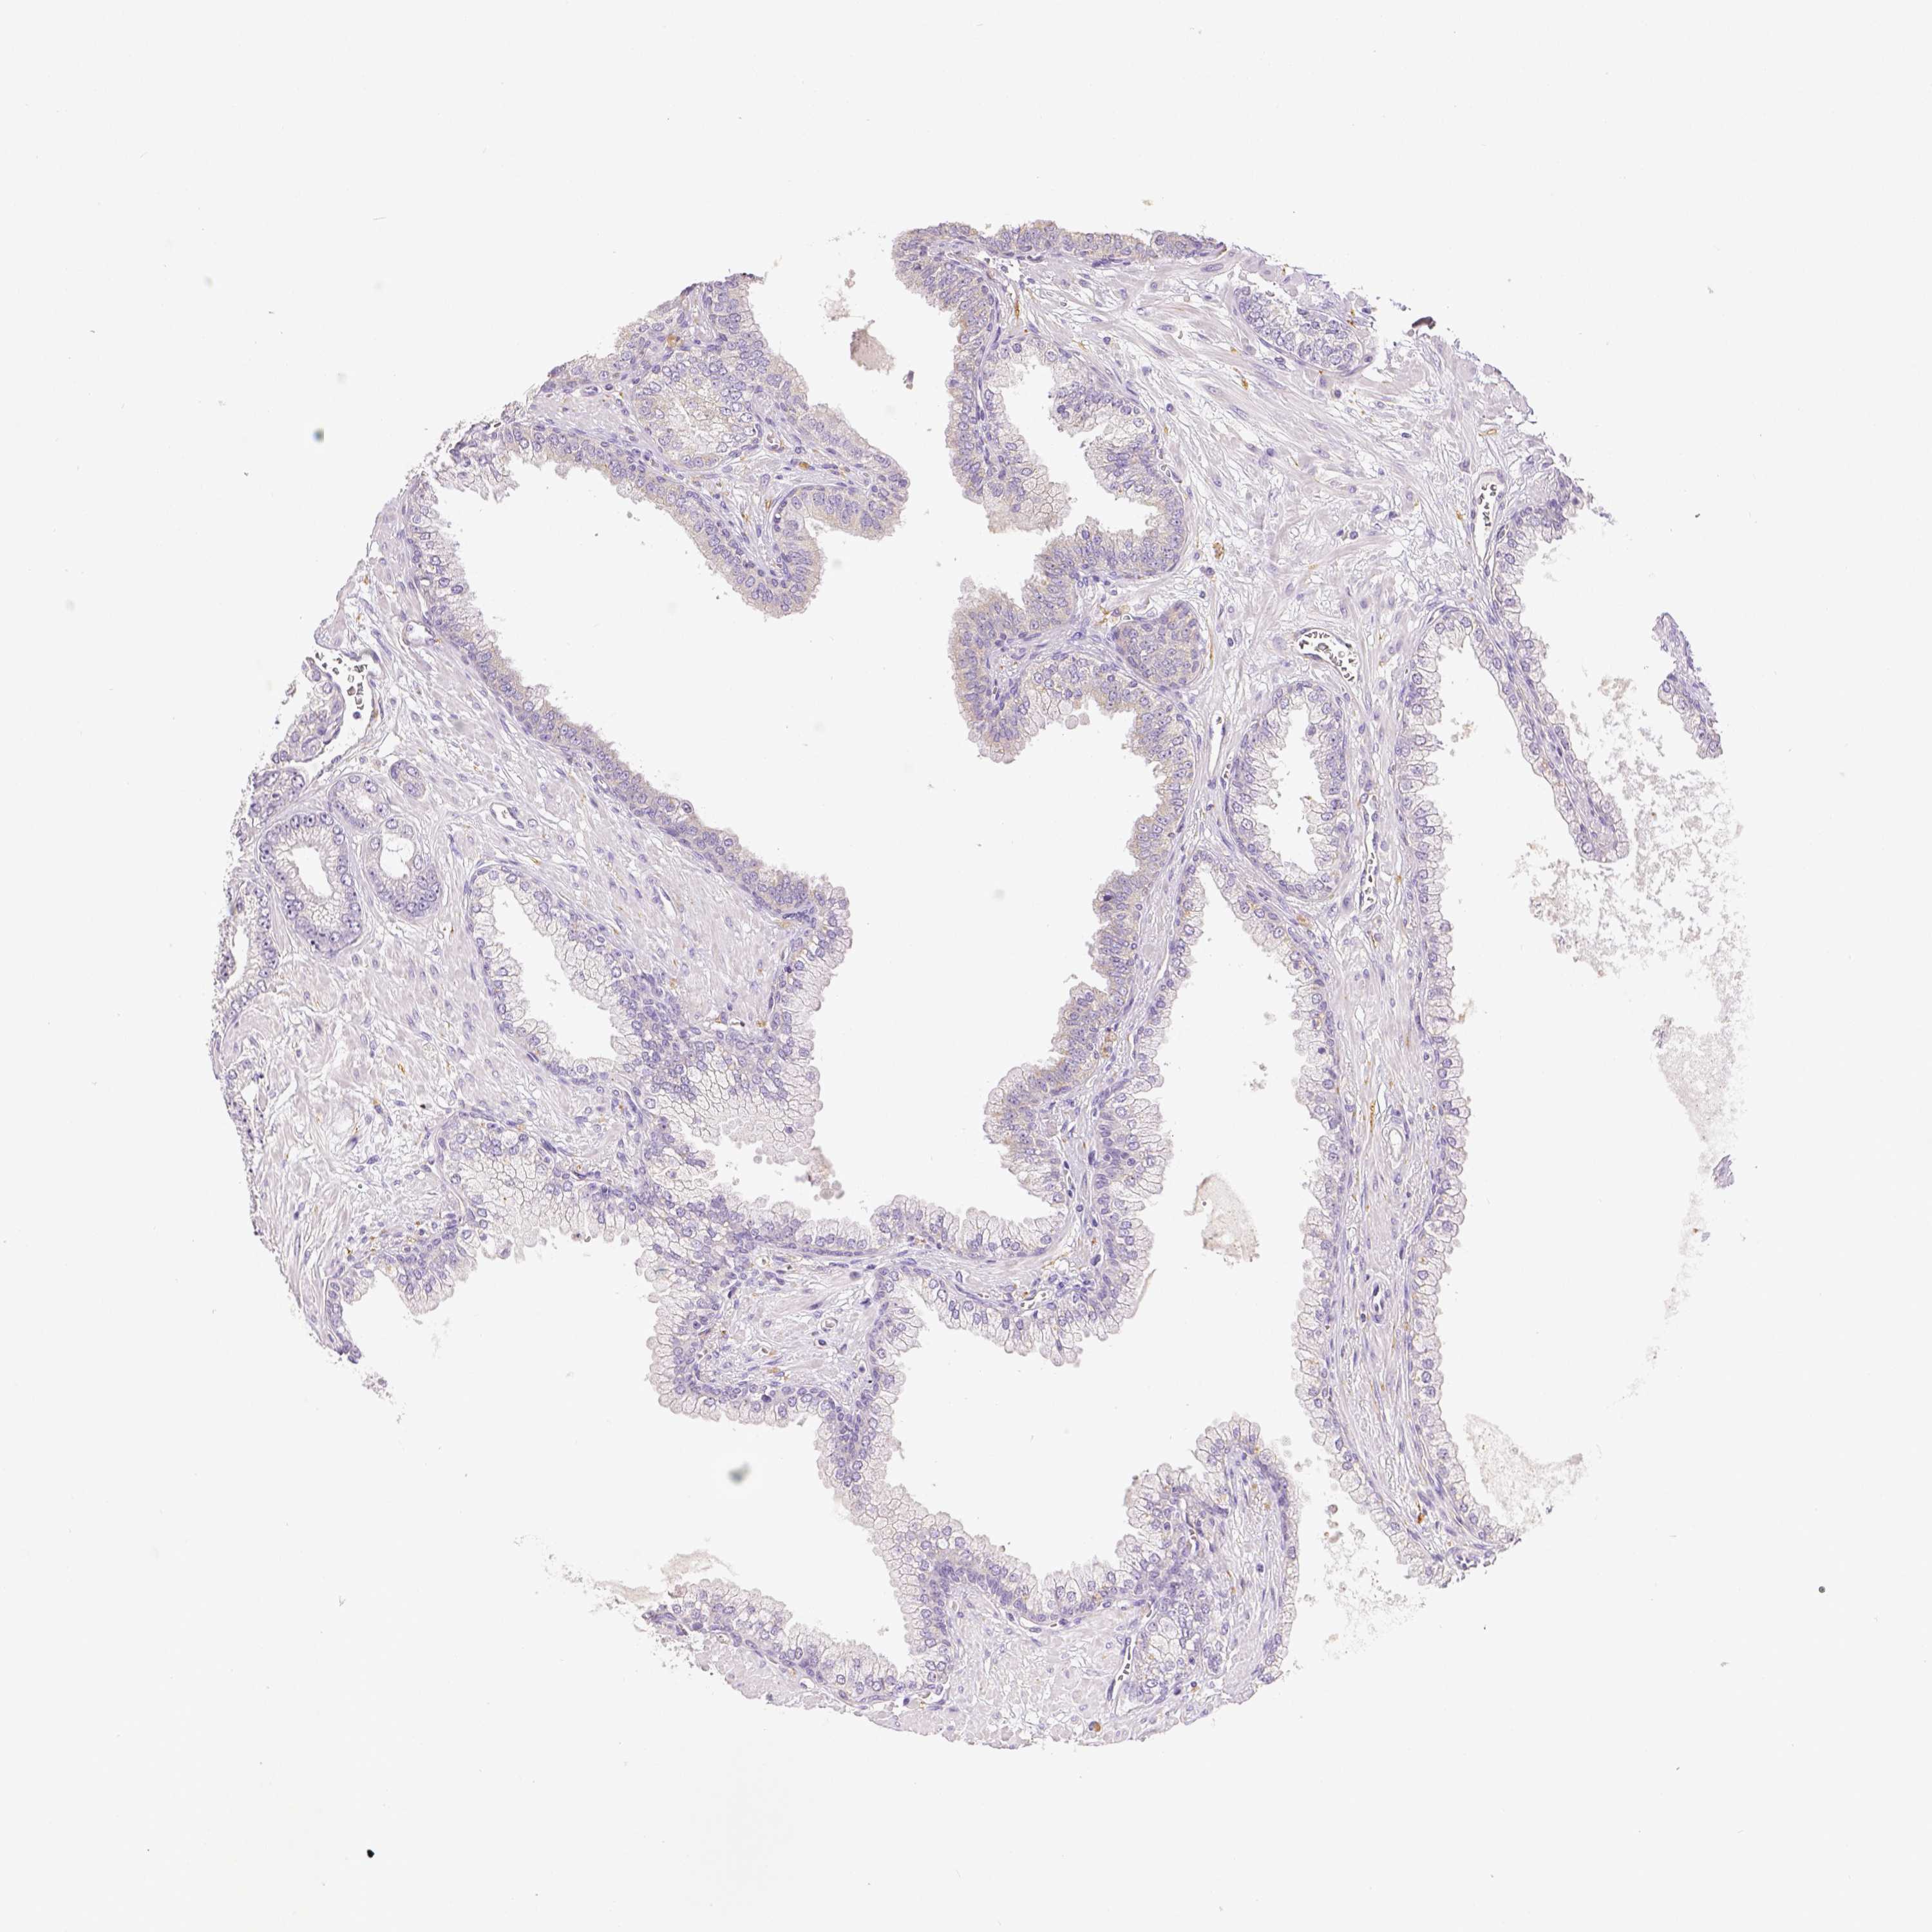

PROSTATE CANCER - Protein expressioni

A mouse-over function shows sample information and annotation data. Click on an image to view it in a full screen mode. Samples can be filtered based on level of antibody staining by selecting one or several of the following categories: high, medium, low and not detected. The assay and annotation is described here.

Antibody stainingi

Antibody staining in the annotated cell types in the current human tissue is reported as not detected, low, medium, or high, based on conventional immunohistochemistry profiling in selected tissues. This score is based on the combination of the staining intensity and fraction of stained cells.

Each image is clickable and will lead to virtual microscopy that enables deeper exploration of all samples and also displays staining intensity scores, fraction scores and subcellular localization as well as patient and tissue information for each sample.

Antibody HPA003733

Adenocarcinoma, High grade

Adenocarcinoma, NOS

Adenocarcinoma, Low grade